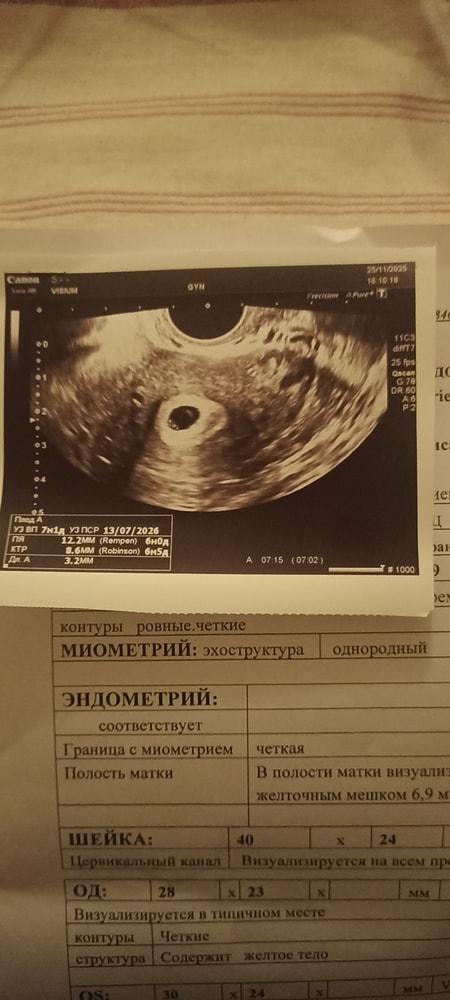

Изменения и болезни во время ББыла коричневая мазня, неделю назад. Легла в больницу. По сроку недель.Сегодня была на контрольном узи, ничего внятного не сказали, все осталось под вопросом, так как эмбриона не увидели. А если нет эмбриона в плодном яйце, то подозрение на замершую. Сказали что вроде как есть, но не уверены что это он.

По узи КТР есть. Желточный мешочек немного большеват, но некоторые врачи его мерят не правильно. Сама с этим столкнулась

Плодное яйцо 7 мм и желточный мешочек 7 мм? Думаю, это настрожоило врача, ведь эмбрион есть (ктр указан) .

Ну так по узи всё нашли же, а для сердцебиения еще рано. Переделайте через неделю, уже будет отчетливо видно 👌🏼

Так у вас же написано ктр 3.2 мм на узи ? Это что?

Как могли измерить то, чего не видно ?